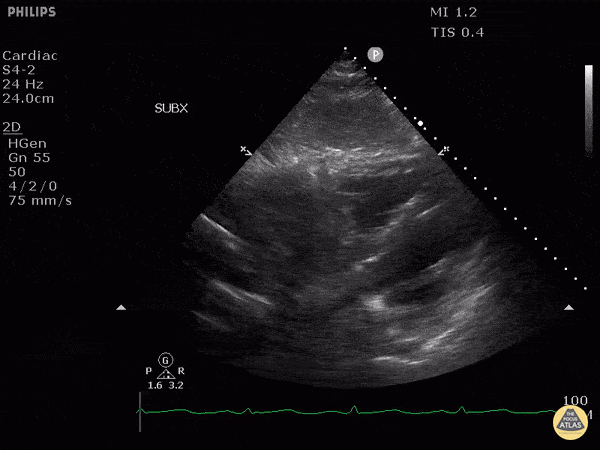

This patient presented to the emergency department after a syncopal episode upon exertion. From this subxiphoid view of their heart, we can see isoechoic structures within their right atrium. This patient was ultimately diagnosed with a cardiac sarcoma. Image courtesy of Robert Jones DO, FACEP @RJonesSonoEM Director, Emergency Ultrasound; MetroHealth Medical Center; Professor, Case Western Reserve Medical School, Cleveland, OH View his original post here